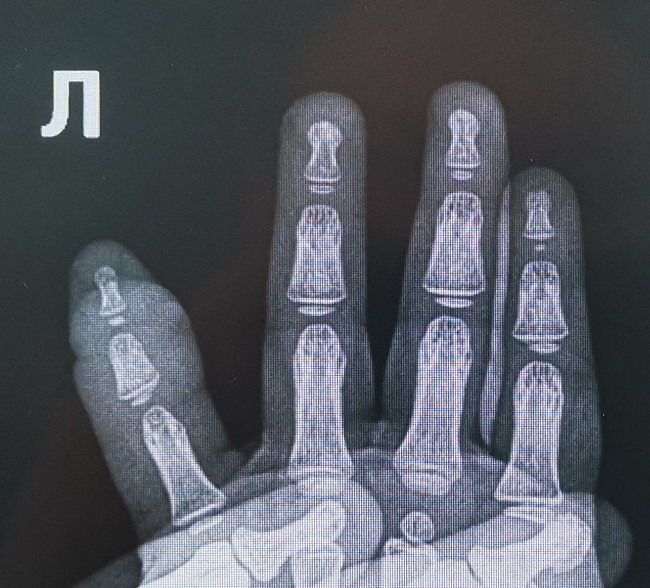

Мама заметила, что у девочки вдруг начал опухать палец на руке. Укус? нет. Ранка или царапина? Тоже нет. Палец распухал все сильнее, покраснел, малышка беспокоилась и хныкала. К счастью, родители не стали тянуть, и повезли ребенка в больницу. Там-то и выяснилось, что у девочки — синдром волосяного жгута, редкий диагноз, сообщает Russian medical server.

Еще немного — и девочка могла бы остаться вовсе без пальца. А все из-за куклы — ее волосы малышка намотала на палец, родители этого сразу не заметили, а волосы все сильнее передавливали кожу, сосуды. В больнице ребенка прооперировали, после назначили антибактериальную терапию, физиолечение. Все прошло хорошо — рана заживала очень быстро, и уже спустя несколько дней ее отпустили домой, к родителям и игрушкам.